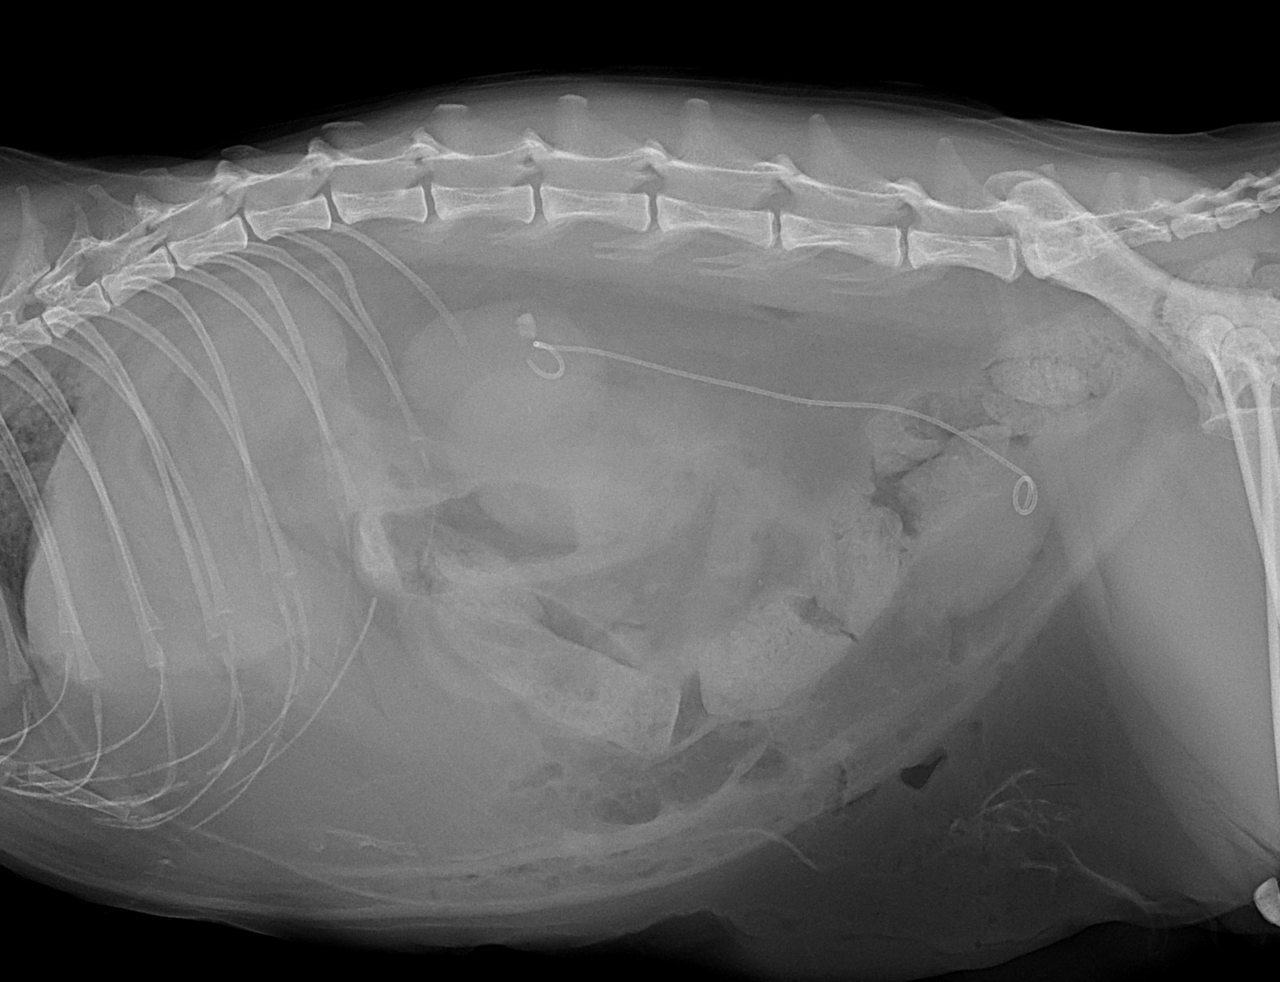

10歳の猫ちゃんの尿管閉塞を外科的に対応して欲しいと、主治医のリクエストがあり対応しました。無麻酔CTで結石の位置、大きさ、左右、個数など詳細を確認しました。右の腎盂拡張、尿管拡張、尿管結石が確認されました。顕微鏡下で右の腎盂〜尿管〜膀胱内に尿管ステントを留置しました。尿管結石の影響で広範囲に尿管の上皮に炎症が起こっています。その結果、尿管壁に線維化、狭窄、そして尿管の蠕動運動の機能低下などが起こります。ステントを入れて尿路を確保したので徐々に腎数値も改善してくるでしょう。また術後にはプレドニゾロンを使って尿管の炎症を抑えることも有効です。